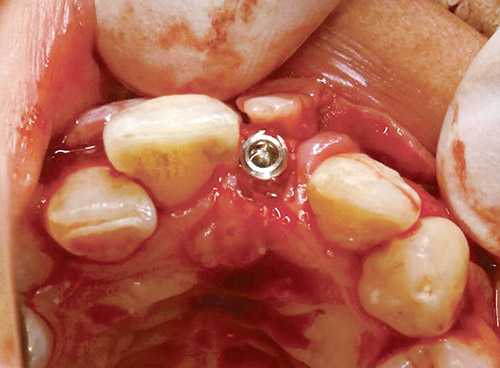

剥離は剥離子と骨が常に90度に保たれるように丁寧に行うことが必要である。埋入は、エレメント(トーメンメディカル社)φ3.5×12.5mmを選択した。

サージカルステントを使用し、ベクトパイロットドリルとベクトツイストドリルにてドリリングを行い、20Nにてラチェットレンチで初期固定を得た。その際、注意すべきことは、ヒーリングキャップの厚みが1mmあるのでその分深く埋入しなければならない。

図11 エレメントφ3.5mm×12.5mmを埋入したところ。 -